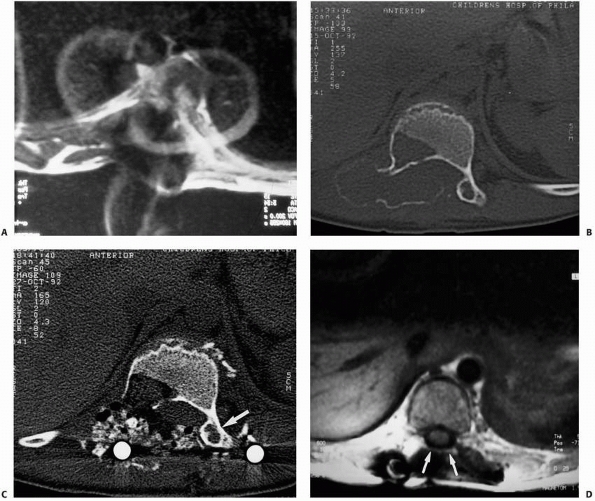

FIGURE 6-6

A 14-year-old boy presented with acute right leg pain following a fall from his bicycle. He reported previous intermittent pain over that same area. On initial plain radiographs (A,B) there is a large, expansile, and destructive lesion in the proximal tibial metaphysis. The bone is mildly expanded and there is a minimally displaced pathologic fracture (arrow). Axial CT image (C) better defines the extensive cortical disruption and soft tissue involvement postfracture anterior-medially. The patient underwent biopsy confirming the diagnosis of aneurysmal bone cyst. After the final pathology report was available, he underwent intralesional excision of the mass with curettage, high-speed burr, electro-cauterization, cryosurgery, and bone grafting with a combination of a strut allograft and crushed cancellous allograft (D,E). (Figures reproduced with permission from the Childrens Orthopaedic Center, Los Angeles, CA.) |

FIGURE 6-8 A 9-year-old boy presented with low back pain and abdominal discomfort. On plain radiographs of the abdomen (A), an expansile lesion involving the left posterior elements of L1 was visualized. Axial T2-weighted MRI (B) and an axial CT scan image (C) show the microfractures at the pedicle and lamina level (arrow)

and the fluid-fluid levels. The patient underwent open biopsy that confirmed the diagnosis of aneurysmal bone cyst, followed by a 4-step approach excision and bone grafting. Limited instrumentation of the spine was performed due to stability compromise (D). (Permission) |

FIGURE 6-9

When dealing with pathologic fractures secondary to tumors or tumor-like processes of the spine, if instrumentation is needed, titanium instrumentation allows much better postoperative visualization with both CT and MRI for the detection of tumor recurrence as compared with standard stainless-steel instrumentation. A. Postoperative MRI of the spine with standard stainless-steel instrumentation showing a large degree of artifact that makes interpretation difficult. B. Preoperative CT scan of a patient with an ABC of the spine. C. Postoperative CT scan of the same patient showing an adequate view of the surgical area. D. Postoperative MRI of a patient with a previous spinal tumor again adequately showing the surgical site to monitor for recurrence or persistent tumor. |